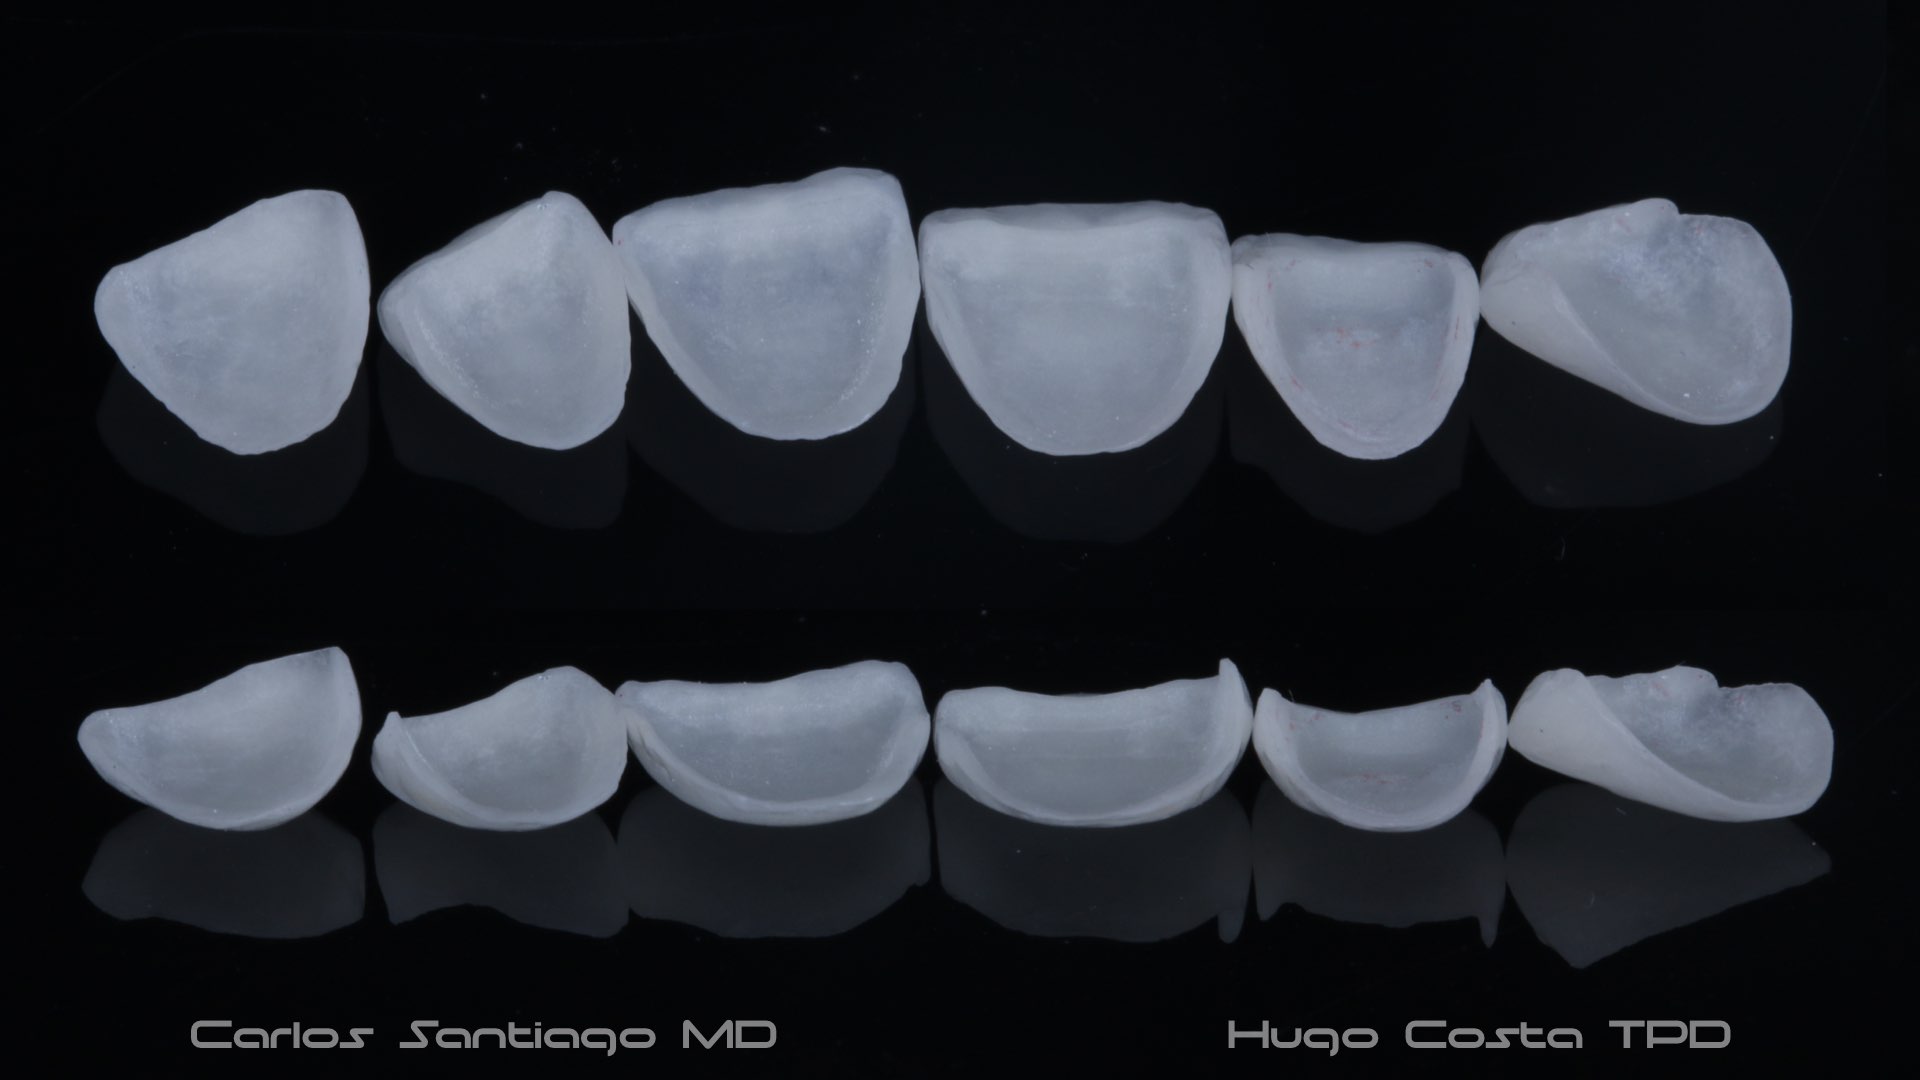

As Facetas Cerâmicas (lentes de contacto dentárias ou laminados), permitem corrigir da maneira mais estética e conservadora possível, problemas de forma e tamanho, côr e posição dos dentes, bem como substituir restaurações antigas e inestéticas.

São aderidas químicamente ao esmalte dentário de uma forma permanente, com o objectivo de melhorar a estética dos nossos pacientes.